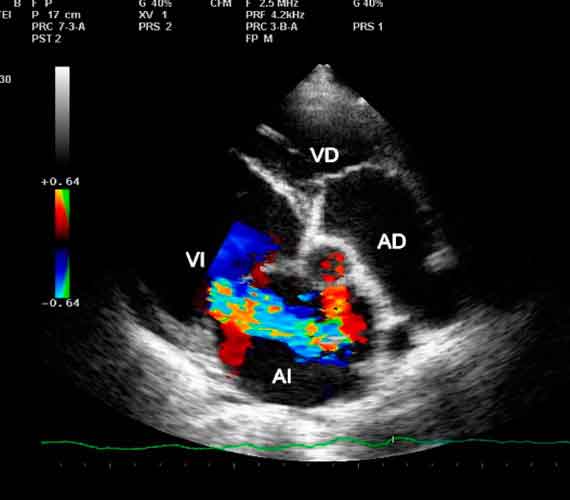

Ecocardiograma

Estudio que emplea ondas sonoras para producir una imagen del corazón que permite ver cómo funciona.